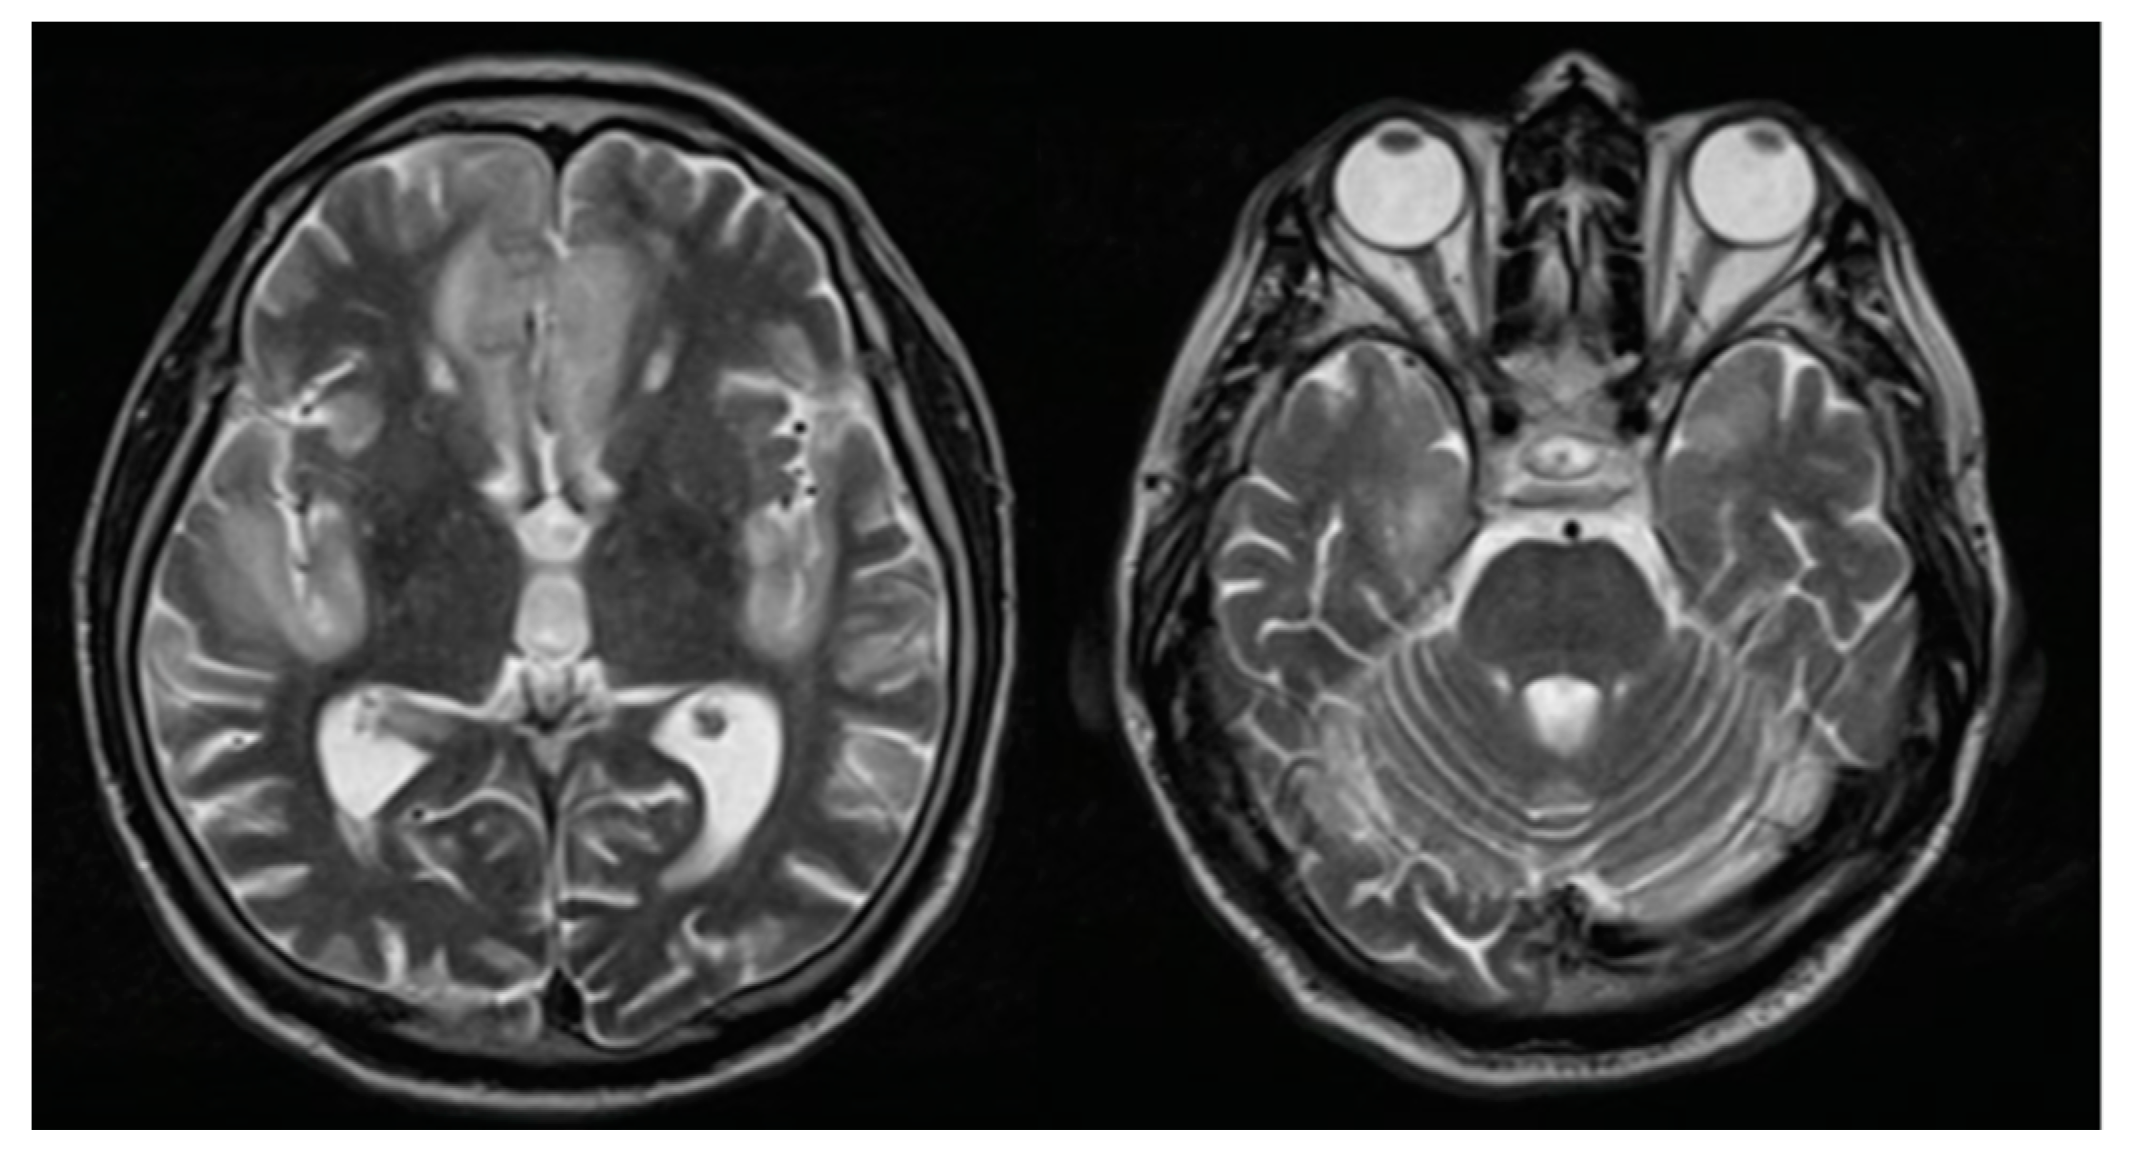

He was evaluated in the emergency room by the medical staff who requested computed tomography (CT) of the brain, evidencing a circumscribed hypodensity in the frontal lobe, deciding his hospitalization. At the clinical examination on admission, the patient was awake, confused, with a partial response to simple commands, without sensory or motor alterations and without signs of meningeal irritation. Due to acute encephalopathy of unidentified etiology, serum, imaging, and cerebrospinal fluid (CSF) tests were performed, ruling out a clinical picture of infectious, metabolic, collagen, or oncological origin. However, a high protein concentration (284 mg/dL) was highlighted, without cellularity or glucose consumption. We performed brain magnetic resonance imaging (MRI) with evidence of circumscribed encephalitis at the anterior frontal and bilateral temporal lobes (Figure 1). The patient received 10 mg/kg of daily intravenous acyclovir for seven days until we discarded a possible infectious cause.

Figure 1.

Brain magnetic resonance imaging: T2 sequence finding hyperintense lesions at the bilateral straight frontal gyri, left cingulate, and insula.

Regarding brain MRI, in most of the previous cases, an image without alterations was presented [6,9,11,12,13], however, one case reported hyperintense images with edema at the hippocampal level [15]. On the other hand, in our case we found hyperintense lesions almost symmetrically. Concerning treatment, in most of the previous reports, methylprednisolone pulses were offered as the first treatment option, obtaining significant clinical improvement [6,9,11,12,14,15], as in our case.